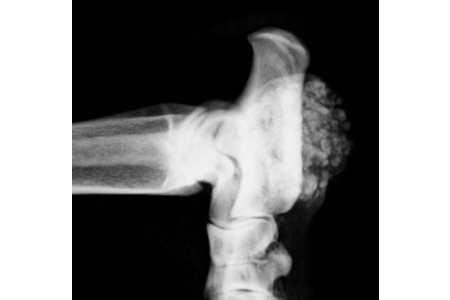

In human medicine a disease is considered to be rare if its incidence is one per 2,000 individuals or less. The majority are genetic in origin and only 30% of the thousands that exist are studied. In...